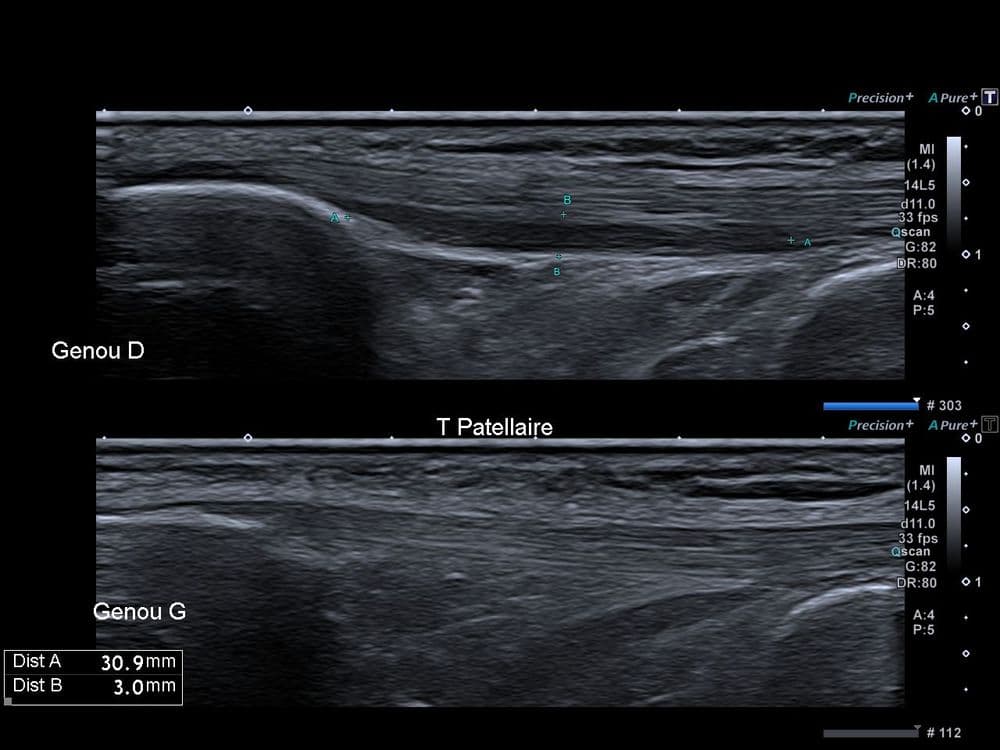

Basketteur professionnel asymptomatique, découverte fortuite d'une séquelle de "Jumper's Knee".

US